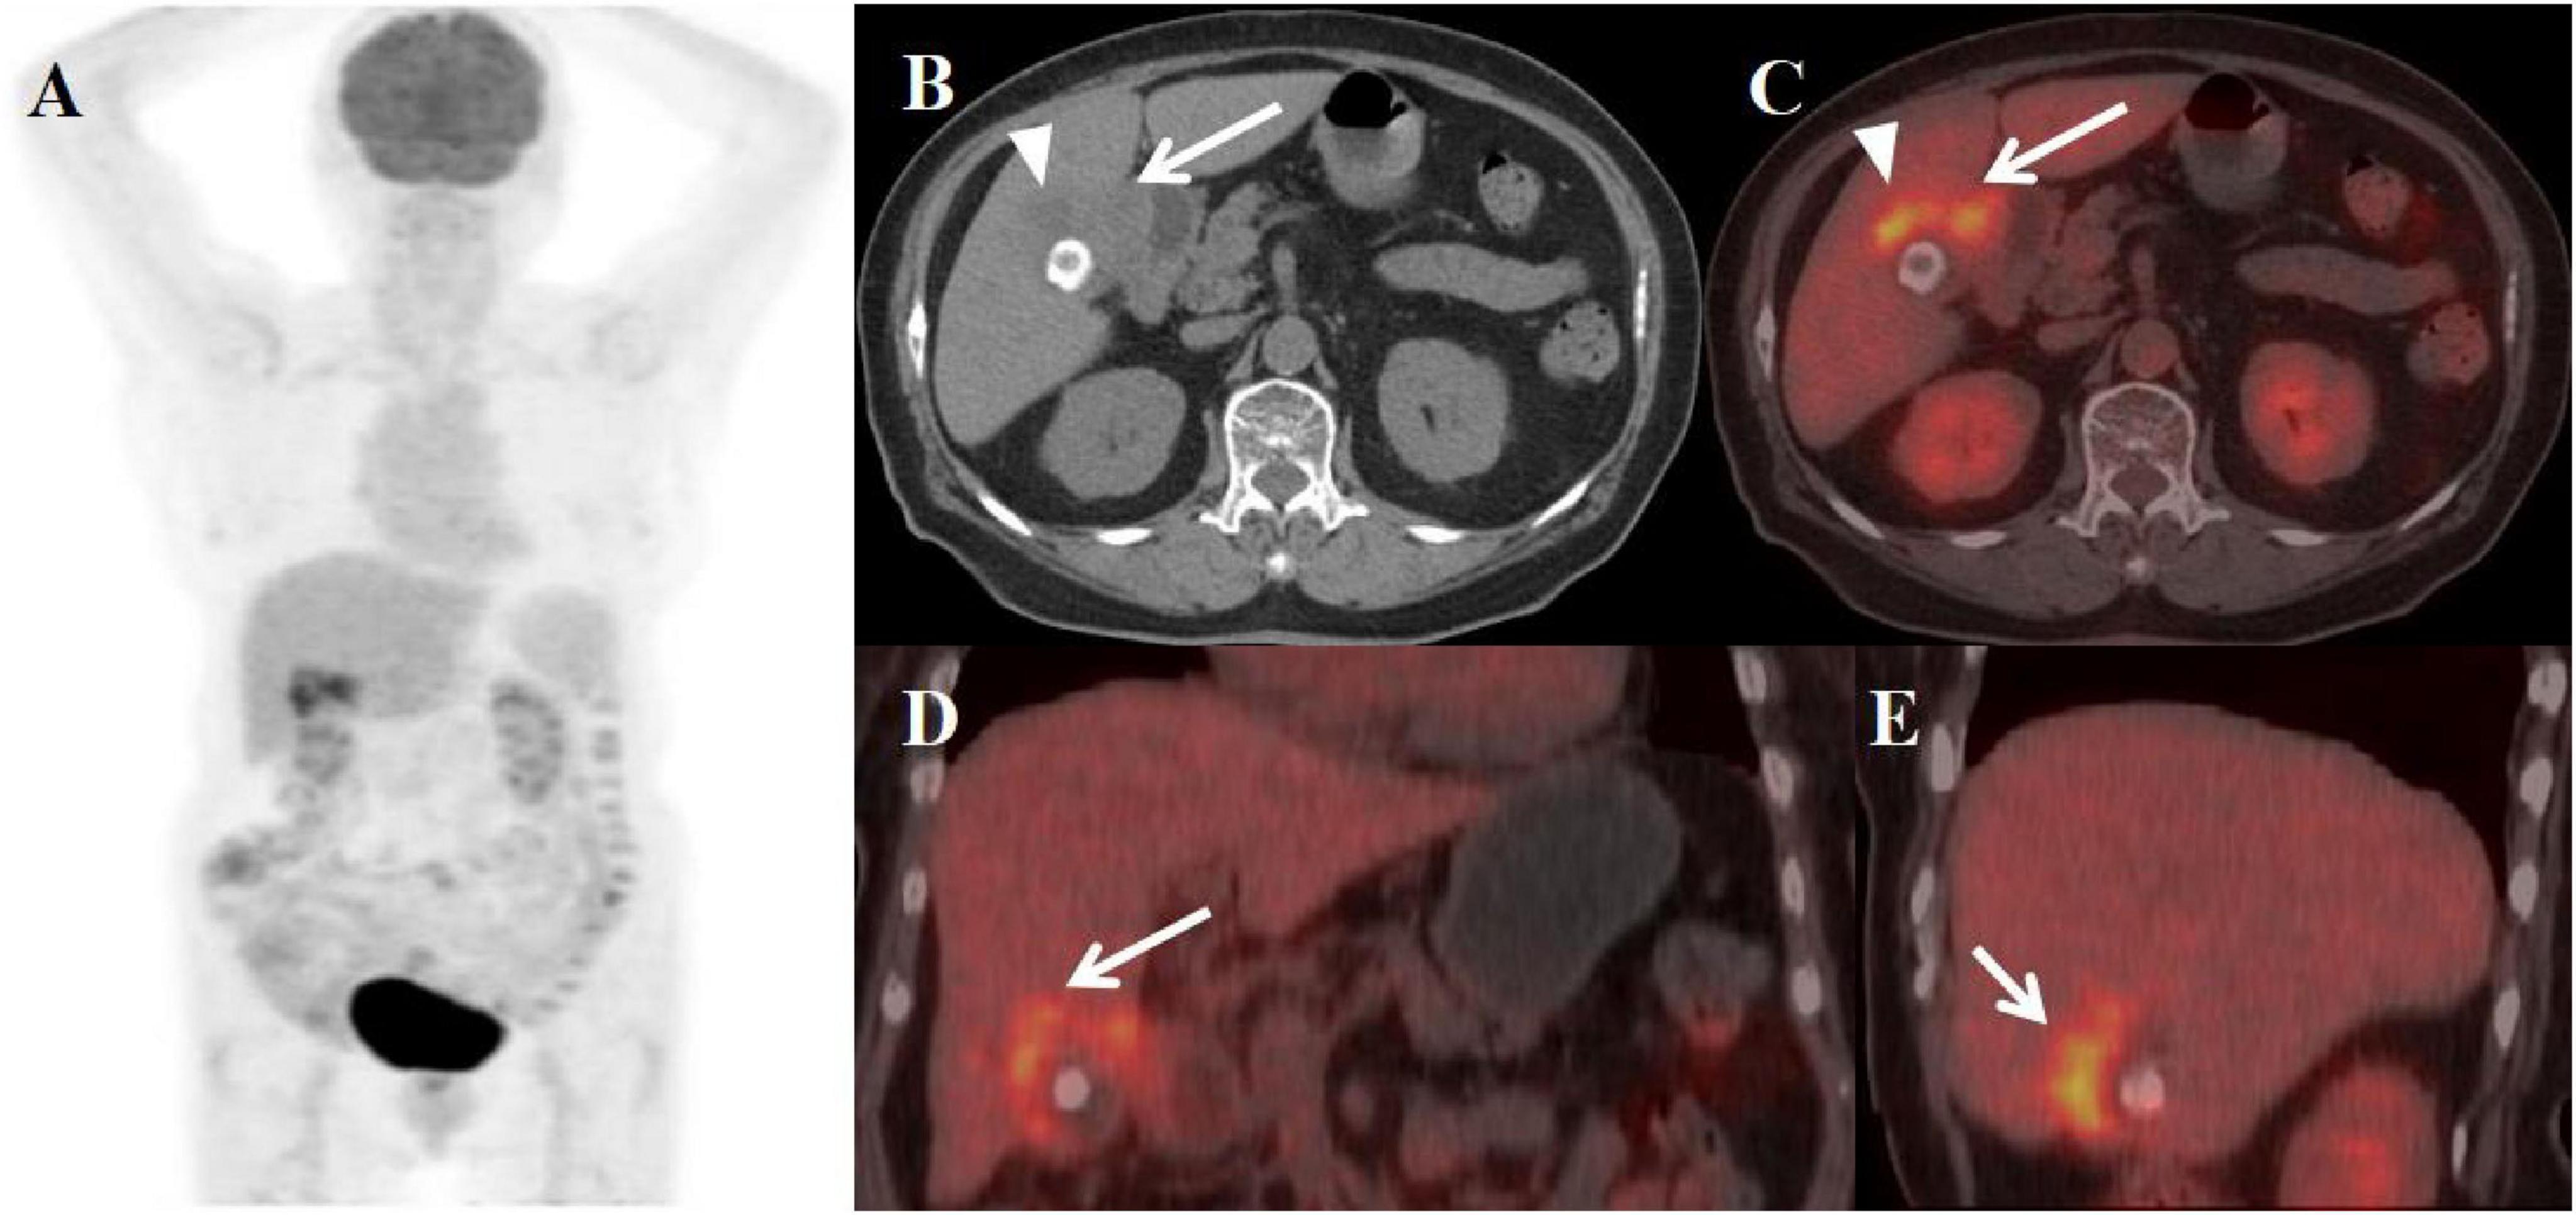

A 49-year-old female patient presented with abdominal pain, jaundice, and weight loss for 20 days before admission. An abdominal MRI scan performed at the local hospital disclosed an abnormal thickening of the gallbladder wall, accompanied by intramural nodules and the presence of enlarged pericholedochal lymph nodes. The boundary between the gallbladder and the liver was indistinct, with no evident signs of liver cirrhosis observed. Furthermore, the scan identified multiple stones within the gallbladder, a stone in the lower portion of the common bile duct, and compression of the upper part of the common bile duct, which led to the dilation of both intrahepatic and extrahepatic bile ducts above the obstruction. The multiphase contrast-enhanced scan images revealed that the thickened gallbladder wall shows mild enhancement during the arterial phase, with progressive enhancement observed in the venous and equilibrium phases. The intramural nodules displayed delayed rim enhancement. Despite undergoing treatments with anti-inflammatory and liver-protective agents at the local hospital, her symptoms showed no significant improvement. In response, a percutaneous transhepatic cholangiographic drainage (PTCD) was carried out. To further clarify the diagnosis and treatment plan, the patient was transferred to our hospital, where a comprehensive series of corresponding laboratory tests and imaging studies were conducted. The results of the inflammatory markers indicated that white blood cell count (WBC), neutrophile granulocyte, and C-reactive protein levels were all within normal limits, with procalcitonin was slightly elevated to 0.18 ng/ml. The levels of key tumor markers were as follows: Cancer Antigen 125 (CA-125) was elevated to 60.04 U/ml, while Cancer Antigen 19-9 (CA19-9) was significantly higher at 433.00 U/ml. Due to the patient’s recent PTCD procedure, the follow-up abdominal CT scan showed no evident obstruction or dilation of the bile ducts. The plain scan detected thickening of the gallbladder wall with low-density intramural nodules, surrounding enlarged lymph nodes, and stones in the gallbladder and the distal common bile duct. The enhancement pattern of the lesions on the contrast-enhanced scan was similar to that seen on the MRI. Subsequently, the patient underwent an PET/CT scan to evaluate the systemic condition. The axial CT and fused axial PET-CT images revealed asymmetric thickening of the gallbladder wall, accompanied by elevated fluorodeoxyglucose (FDG) uptake, with a maximum standardized uptake value (SUVmax) of 7.5. Enhanced FDG uptake was observed in several enlarged lymph nodes near the gallbladder fossa, reaching a SUVmax of 3.5. The intramural nodules showed no significant uptake of FDG (Figure 1). Given the imaging findings presented, a suspicion of GBC with hepatic invasion and lymph node metastasis was raised. After discussing the situation with his family, they agreed to proceed with a surgical procedure. The patient subsequently underwent a 5-hour-long procedure, comprising laparoscopic exploration, open partial hepatectomy (anatomical resection of segment IVB and V), choledochotomy, cholecystectomy, bilateral hepaticojejunostomy with Roux-en-Y anastomosis, and lymph node dissection. Considering the possibility of gallbladder cancer invading segment IV of the liver and the porta hepatis, and with no evidence of tumor metastasis in the other abdominal organs, an open abdominal surgical approach was undertaken for treatment. The intraoperative pathology evaluations uniformly pointed to chronic inflammation. Postoperative pathology confirmed the diagnosis of xanthogranulomatous cholecystitis, as well as reactive hyperplasia of regional lymph nodes.

Figure 1. Female, 49 years old. (A) (whole body MIP), (B–E) (Axial CT and fused axial PET-CT), (F–H) (axial, multiphasic contrast-enhanced CT), (I) (axial, MRI-T2WI), (J) (axial, enhanced-MRI-delayed phase), and (K) (H-E × 40). 18F-FDG PET/CT Imaging Findings: Thickening of the gallbladder wall with indistinct boundaries from the liver, accompanied by increased FDG uptake with a SUVmax of 7.5 (B–E, arrow). Additionally, several enlarged lymph nodes in the vicinity showed similar heightened FDG uptake, with an SUVmax of 3.5 (D, E, arrow ↑). The intramural nodules, however, did not display significant FDG uptake (B, C, arrow ▲). On multiphasic contrast-enhanced CT scans, there was progressive delayed enhancement of the gallbladder wall (F–H, arrow↑), along with marginal enhancement of the intramural nodules (arrow ↑). The CT values for the non-contrast scan phase, arterial phase, venous phase, and delayed phase were 40, 52, 75, and 89 HU, respectively. The abdominal MRI revealed irregular thickening of the gallbladder wall (I, arrow ↑) accompanied by gallstones. The intramural nodules appeared as hyper-intense on T2WI (arrow ▲). Contrast-enhanced imaging demonstrated delayed enhancement of the gallbladder wall (J, arrow ↑), with rim-enhancement of the intramural nodules (arrow ▲). Histopathological analysis confirmed XGC, showing foamy histiocytes intermingled with scattered lymphocytes, encircled by phagocytosed bile, in the absence of malignant cells (K).